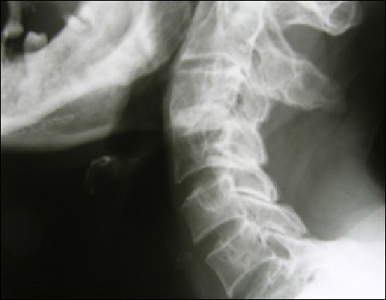

A simple slip when descending the flanks of Skiddaw in 2009 had seemed innocuous enough at the time, it was only a couple of feet as the whole group took it in turns to disappear from sight as we found the drainage channels hidden by the chest high vegetation. Over the next few weeks I developed a range of symptoms from pins and needles in my left arm to an inability to fully control my left leg and balance. With a family history of heart problems the obvious concern was that I was continuing the family tradition of heart attacks - so it was off for a series of ECGs. As the symptoms progressed and the tests came back fine, first the heart scans and then blood tests for an unlikely vitamin deficiency all that was left was an MRI scan. The results of the MRI would turn out to be life changing. High up in my neck the disc between the C3 and C4 vertebra had slipped through the cerebrospinal fluid (CSF) and was almost 50% of the way into my spinal cord. The pins and needles and unsteadiness were the result of nerves being cut or compressed and surgery was the only solution. Thanks to the neurosurgeons at Salford the immediate danger was averted by what's called an anterior cervical discectomy and fusion, where the disc is replaced with bone grafts or a synthetic replacement and the vertebrae on either side are fused , but the damage was already done. Nerves that had been compressed too far were irreparable and in the long tern the genetic degenerative disc disease that had helped cause the problem wasn't going to get any better.